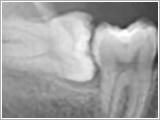

歯周病

歯を失う最も多い原因は虫歯と歯周病です。

成人の約8割の方が歯周病に罹患していると言われています。いつまでも健康な自分の歯で過ごしたい。誰もがそう思っているはずです。まだ歯周病になっていない方には予防的処置を、すでに歯周病の方にはなるべく抜かずに歯を長持ちさせる治療を行います。